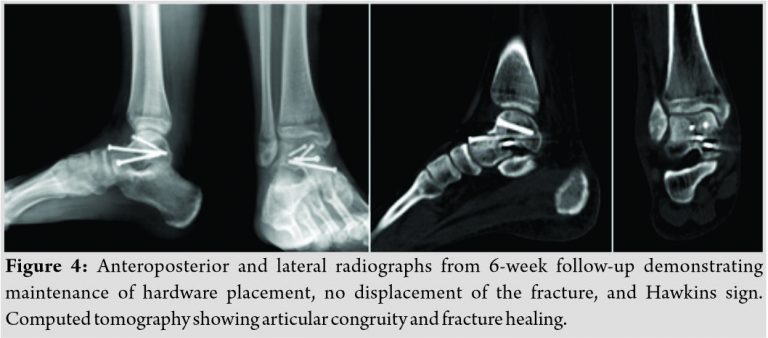

The radiological evaluation at 8 weeks revealed fracture healing with reduction maintained. A positive Hawkins sign was observed, indicative of intact blood supply. No degenerative changes of subtalar or talonavicular joints were observed on radiographs at 6-month follow-up (Fig. 4). At 6-month follow-up, one of the positive findings in clinical evaluation was a slight deficit of strength in supination, 4/5 according to the Medical Research Council scale. The inversion subtalar joint movement was also slightly restricted, compared to contralateral. However, the patient showed an important clinical improvement with rehabilitation program.

There were no swelling, no tenderness or pain, and no scar-related complaints. No differences in the hindfoot alignment were seen (Fig. 5).